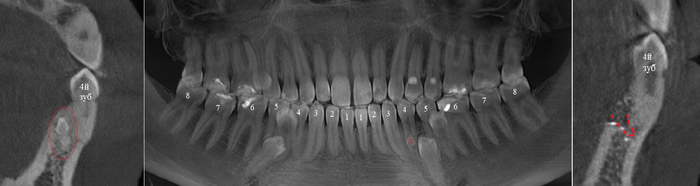

Контрольная ортопантомограмма:

Прицельный снимок:

Я согласен, что эстетика хромает. Давно пора менять временную коронку на постоянную, что улучшит результат. Но, как я говорил, все упирается в финансы.